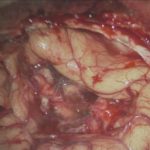

術中写真

摘出 前

摘出 中

摘出 後